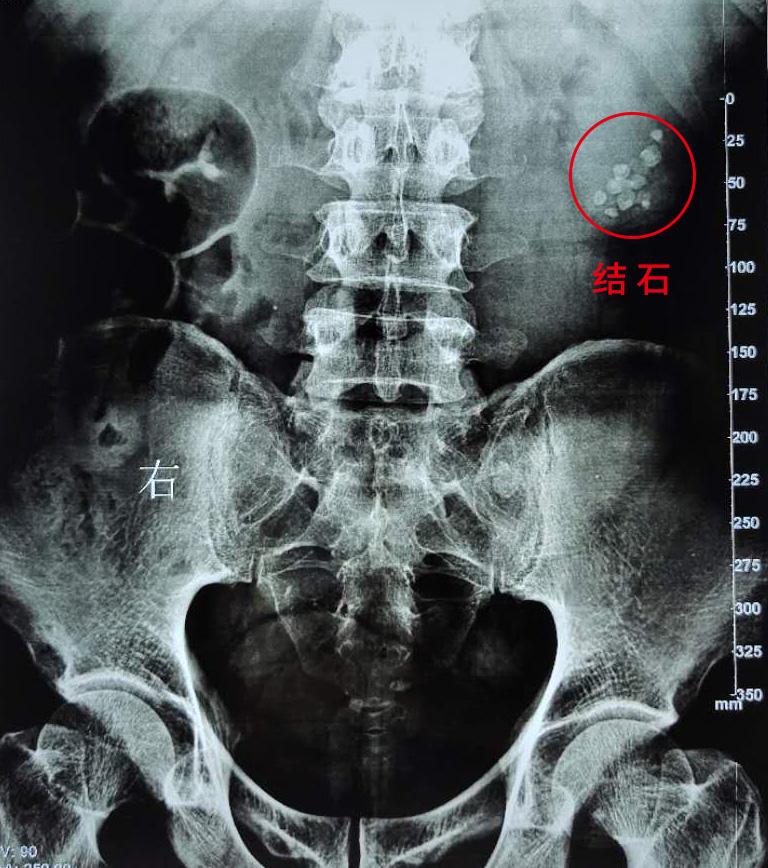

高大叔左肾里堆积的多颗结石,清晰可见